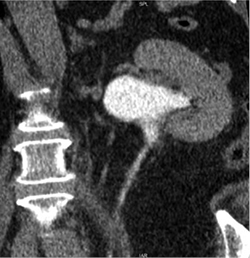

2019 m. gegužės 7 d. (praėjus apie 6 mėn. po operacijos) atlikta kompiuterinė tomografija (4 pav. B). Kairiojo inksto kolektorika kiek prasiplėtusi, geldelė iki ~42 mm pločio, kontrastinę medžiagą (k/m) skiria laiku, kontrastuojasi, k/m nuteka šlapimtakiu į šlapimo pūslę. Kairysis šlapimtakis neprasiplėtęs, proksimalinėje dalyje jo spindis iki 5,5 mm diametro, distalinėje dalyje – iki 7 mm. Ties šlapimtakio proksimaline dalimi matyti infiltruoti aplinkiniai audiniai (vertinama kaip pakitimai po buvusios operacijos). Kitų pakitimų šlapimo takuose nenustatyta.

2019 m. spalio 9 d. (praėjus apie 12 mėn. po operacijos), atlikus kompiuterinę tomografiją, matyti, kad kairiojo inksto geldelė mažiau išplėsta – iki ~26 mm pločio (buvo iki 42 mm), PUJ spindis – apie 2,5 mm pločio, distaliau šlapimtakis neišplėstas, jo spindis iki pat šlapimo pūslės išmatuojamas 3,5–5 mm, sienelės plonos, rentgenokontrastinių akmenų nematyti (4 pav. C). Ties PUJ periureteriniuose audiniuose – fibroziniai pakitimai, perinefriniuose audiniuose – dorzaliai riebalinio audinio ribotos pooperacinės sankaupos.

A

B

C

4 pav. Kompiuterinė tomografija (A – prieš operaciją; B – praėjus 6 mėn. po operacijos; C – praėjus 12 mėn. po operacijos)